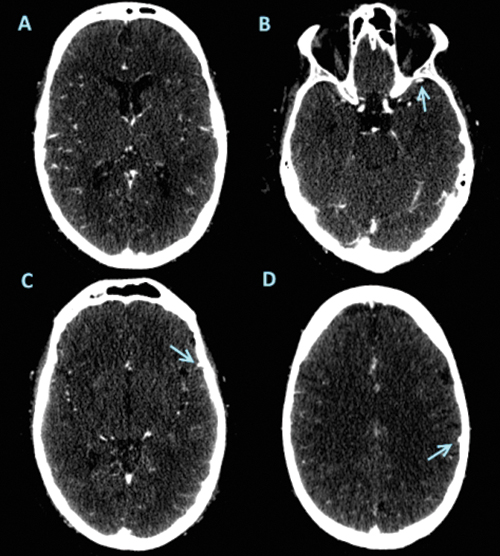

Images from baseline CT angiography in 61-yearold man

Images from baseline CT angiography in 61-yearold man with right-sided segment M1 occlusion. (A) Image shows abundant arterial collateral flow in affected hemisphere (grade 3). Patient hadmoderate disability 90 days after IAT (mRS score, 4). (B–D) Images in unaffected hemisphere show full opacification (arrow) of sphenoparietal sinus (B), superficial middle cerebral vein (C), and vein of Labbé (D). However, opacification was absent in all three cortical veins in affected hemisphere. This resulted in a COVES of 0 for this patient. Images courtesy of Ivo G. H. Jasen, MD.